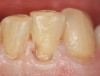

Figure 5   Final composite restorations of the four maxillary incisors.

Figure 5

Case 2 demonstrates composite restoration following orthodontics. Surface concavities on the facial of the lateral and central incisors, papillae loss between the central incisors, severe incisal wear on left central incisor, and a poorly shaped right lateral incisor were restored with composite. Placement of a clear matrix that reflected the gingiva allowing subgingival bonding and composite placement closed the gingival embrasure between the central incisors (Figure 4 and Figure 5).